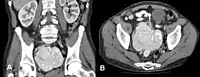

Для оцінки та визначення правильного підтипу показані різноманітні лабораторні тести та візуальні дослідження, але всі три підтипи потребують гістологічного дослідження зразка біопсії із лімфатичного вузла.

Візуалізація в першу чергу корисна для визначення реакції на терапію. Візуалізацію всього тіла слід проводити у всіх пацієнтів. Як правило застосовують FDG-позитронно-емісійну томографію.

Ексцизійна біопсія лімфатичного вузла повинна проводитися на максимально збільшеному, найбільш легкодоступному вузлі. Якщо повна ексцизійна біопсія лімфатичного вузла неможлива, можна зробити біопсію з голкою, керовану за допомогою комп'ютерної томографії. Тонкоголкова аспірація у такій ситуації не буде доцільною. Отриманий біоптат слід направити на морфологічну оцінку, тестування на вірус герпеса 8-го типу, проточну цитометрію, цитогенетику, флуоресцентну гібридизацію in situ для досліджень лімфоми та перегрупування генів В-клітин.